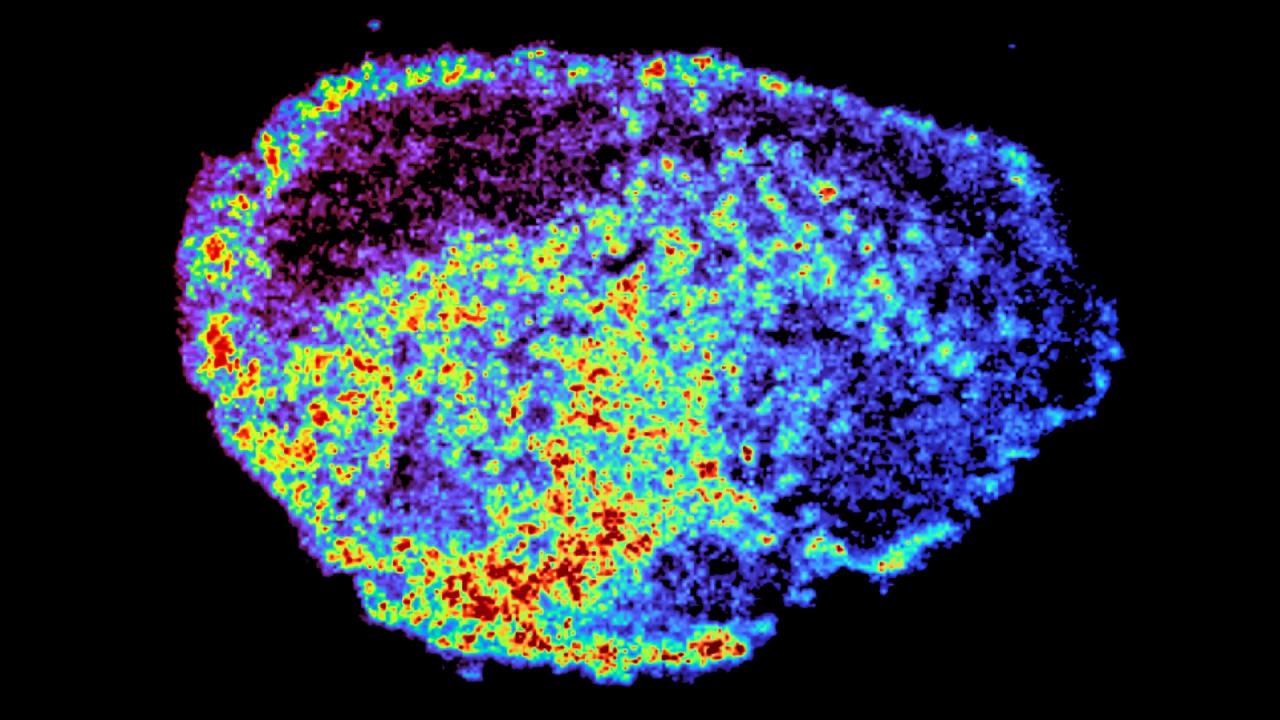

A kutatók friss tumorszeleteken vizsgálták a gyógyszerek eloszlását, majd tömegspektrometriás képalkotással részletes, helyenkénti térképet hoztak létre a gyógyszerfelhalmozódásról. Közben azt is nyomon követték, hogy a szöveten belül, az eltérő gyógyszerszintű területeken milyen gének aktívak. Meglepő módon hatalmas különbségeket találtak a gyógyszereloszlásban, akár egyetlen daganaton belül is, miközben minden beteg ugyanakkora dózist kapott.

A kutatók rájöttek, hogy a lizoszómák – ezek az apró sejten belüli „újrahasznosító gyárak” – alapvető szerepet játszanak a gyógyszerek egyenetlen megoszlásában. Egyes PARP-gátlók ezekbe a sejtszervecskékbe szívódnak fel, ahol a gyógyszermolekulák „csapdába” esnek, majd később lassan felszabadulnak. Így a lizoszómák rejtett tartalékként funkcionálnak, helyenként növelve, máshol csökkentve a gyógyszerszintet. Fontos különbség, hogy nem minden gyógyszer hajlamos erre: például a rucaparib és a niraparib ilyen módon viselkedik, míg az olaparib nem.

A kutatásból az is kiderült, hogy még egyetlen sejt szintjén is hatalmas eltérés lehet a gyógyszer felhalmozódásában, és éppen ezek a lizoszomális tárolók felelnek a hosszabb távú, egyenlőtlen hatásért.